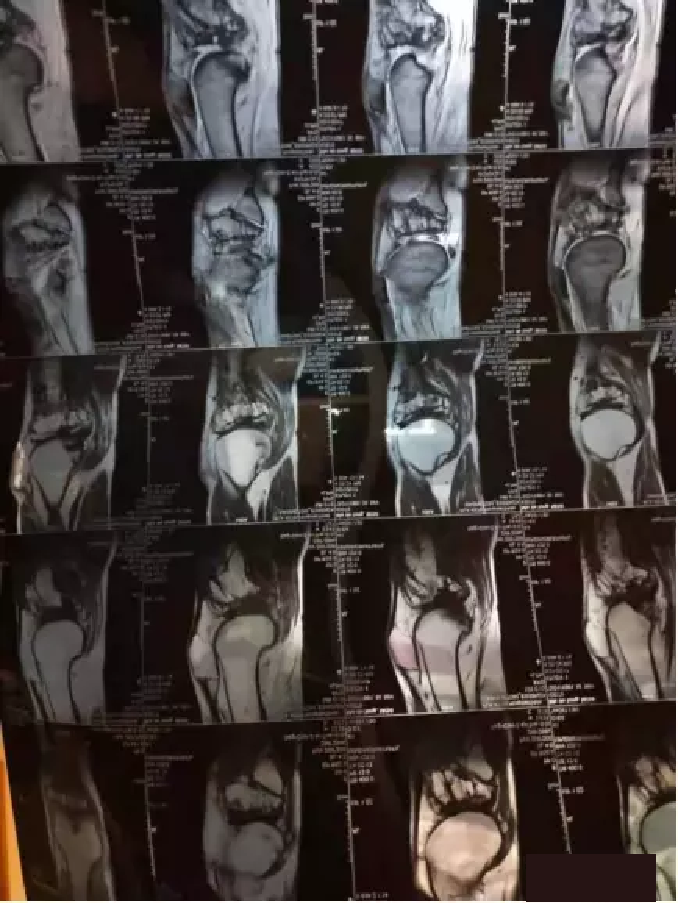

50多(duō)歲的(de)孔先生(shēng),右膝關節患病多(duō)年(n©↕✘ián),疼痛難忍。當初,由于右膝內(nèi)側半月(yuè)闆後角撕裂,醫(yī)生∞€★&(shēng)建議(yì)手術(shù)治療,擔心後遺症的(de)馬先∏γ生(shēng)沒有(yǒu)同意。後來(Ω→←lái),于去(qù)年(nián)4月(yuè)至6月(yuè),連續三個(gè)月(yuè)采↓∑取膝關節幹細胞調理(lǐ)後,關節疼痛明(míng)顯緩解,病痛減輕,&≥$ 孔先生(shēng)也(yě)恢複了(le)正<  ÷常生(shēng)活。

圖片

“孔先生(shēng)的(de)檢查确診報(bào)告”